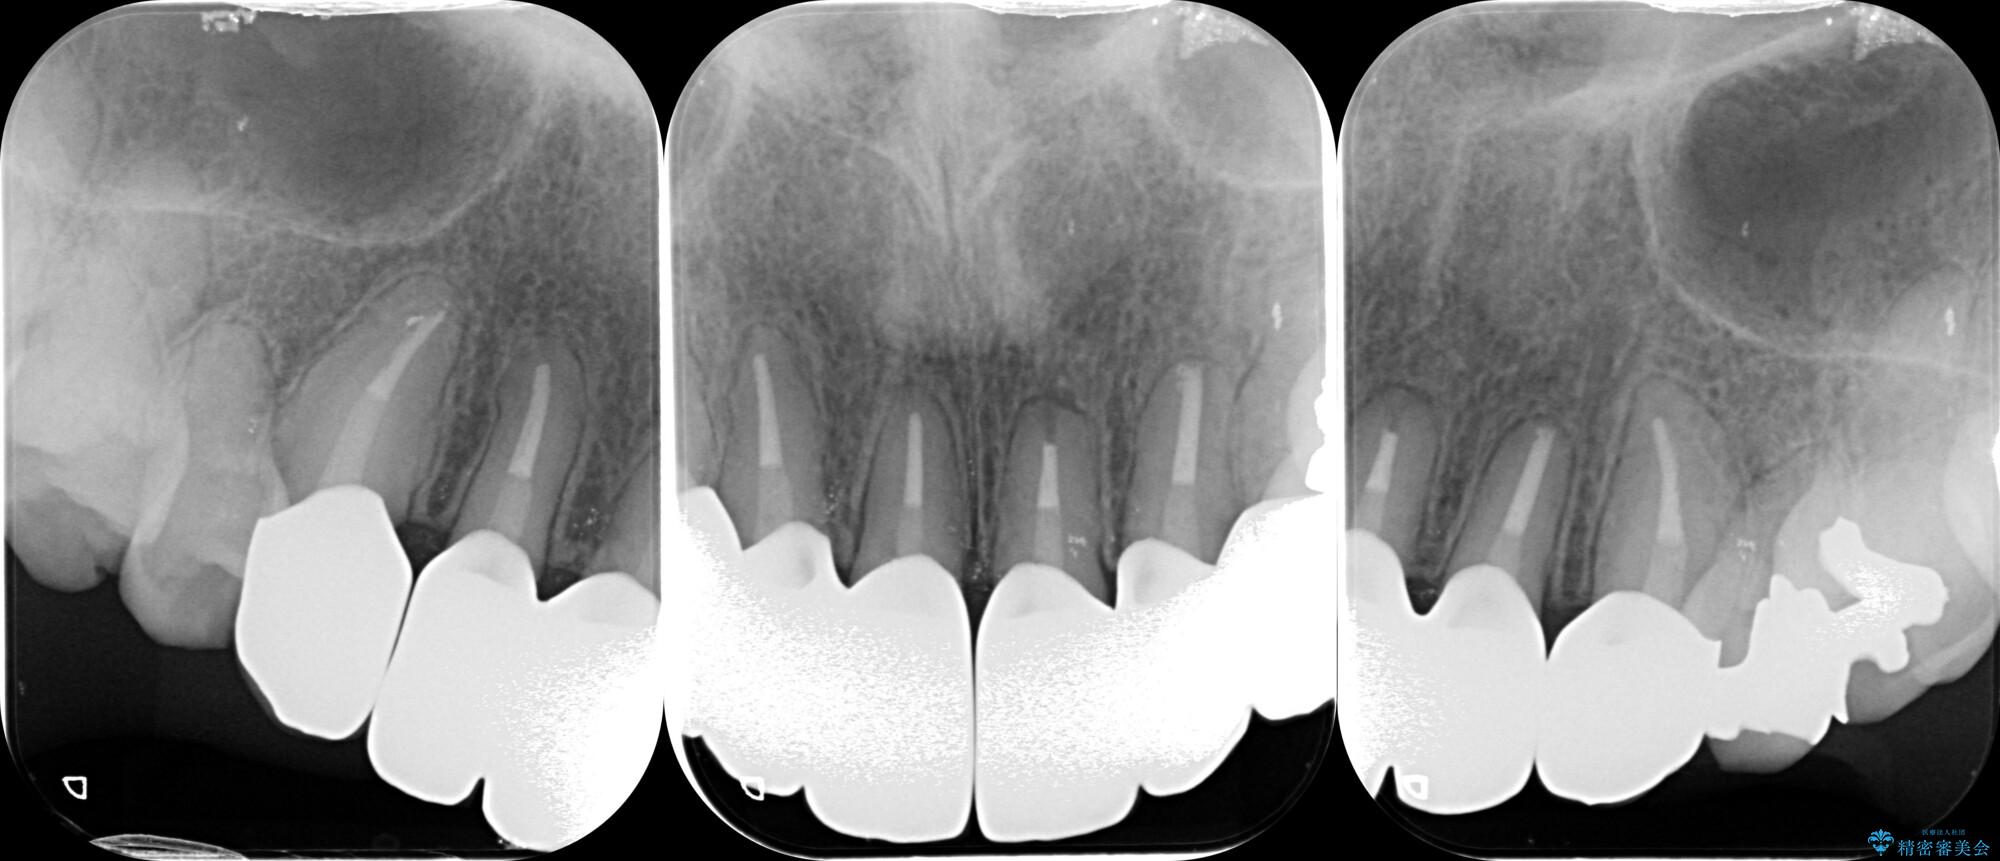

装着されていたセラミックを除去したところ、歯ぐきの奥深くまで歯牙は削られ、歯ぐきの炎症・出血が著しくみられる状態でした。

この状態で再度セラミッククラウンの作製・装着を行ってもまた同じ状態となってしまうため、歯周外科を行い歯ぐきの状態を整備したのちセラミッククラウン治療をおこなっていきます。